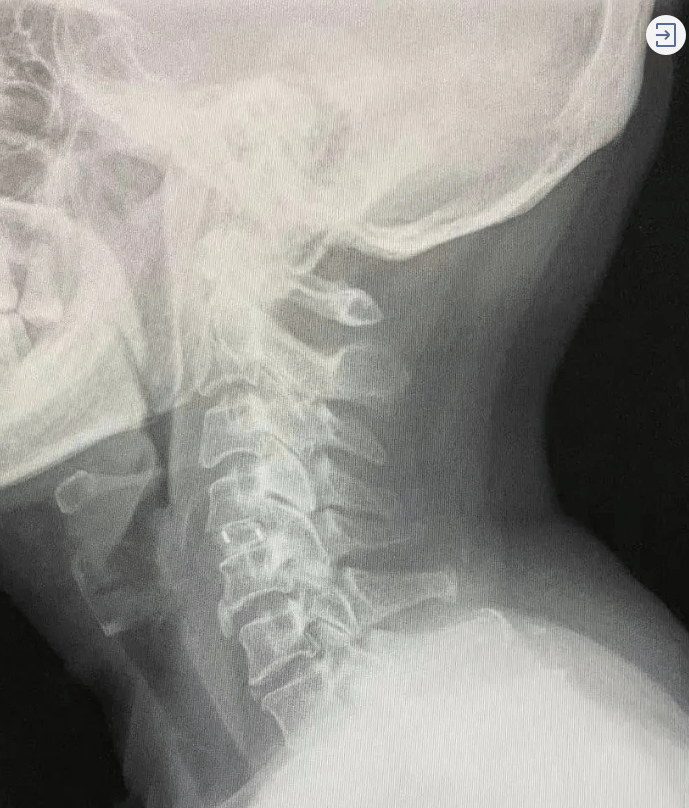

今年8月初 , 一天早晨醒来 , 吴阿姨突然发现左臂、左肩抬不起来 , 完全使不上力 , 因为并没有红肿疼痛的感觉 , 就以为是累了 , 休息了两天 , 仍没有好转 。 吴阿姨急忙赶到当地医院 , 医生考虑为左肩关节问题 , 拍片后却发现并没有明显病变 。 当地医院建议吴阿姨再到省级大医院看看 , 吴阿姨便来到了浙江大学医学院附属第一医院 。

文章图片

对吴阿姨经过初步检查后 , 结合她喜欢刷视频的习惯 , 医生判断造成吴阿姨左肩无力的原因很可能在颈椎 。

“颈椎病的表现很多 , 不一定就是颈椎酸痛、头晕难受 , 像肩膀疼痛、无力 , 上肢放射状疼痛 , 双手不灵活(如拿不住筷子、不能自如扣纽扣、打字等) , 走路有踩棉花感 , 运动能力下降 , 无故摔倒等 , 都可能提示颈椎病 。 ”骨科金永明副主任耐心地向吴阿姨解释道 。

医生说 , “如果是早期颈椎病 , 可以先进行保守治疗 , 但像吴阿姨这样已经压迫到了神经 , 唯一的治疗办法就是手术 。 ”